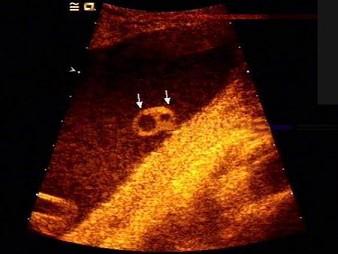

如图,为一孕妇34周时,羊水内漂浮所见管道结构(横切),最可能的诊断是?(?)A.脊柱裂B.脑膜膨出C.淋巴管囊肿D.单脐动脉E.正常图像

问题 如图,为一孕妇34周时,羊水内漂浮所见管道结构(横切),最可能的诊断是?(?)

选项 A.脊柱裂 B.脑膜膨出 C.淋巴管囊肿 D.单脐动脉 E.正常图像

答案 D